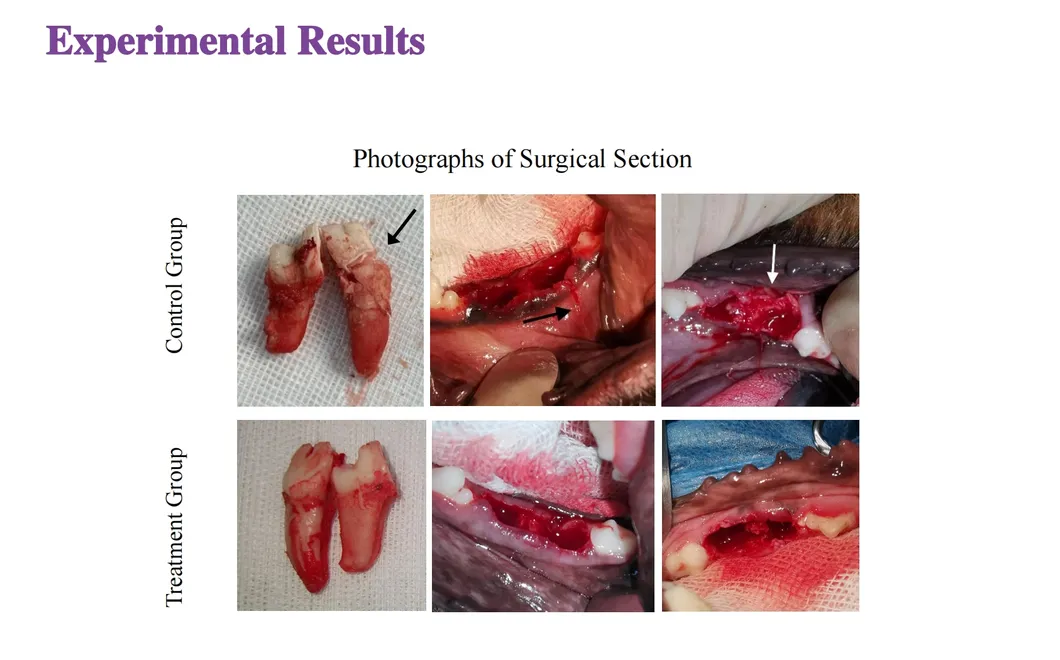

In this groundbreaking study, dogs were selected to assess the effectiveness of the Golden Cudgel-Pneumatic Dental Elevator Kit. Researchers meticulously documented physiological parameters, extraction duration, and socket damage compared to traditional manual devices. The data provides profound insights into the superior performance and efficiency of these advanced dental tools.